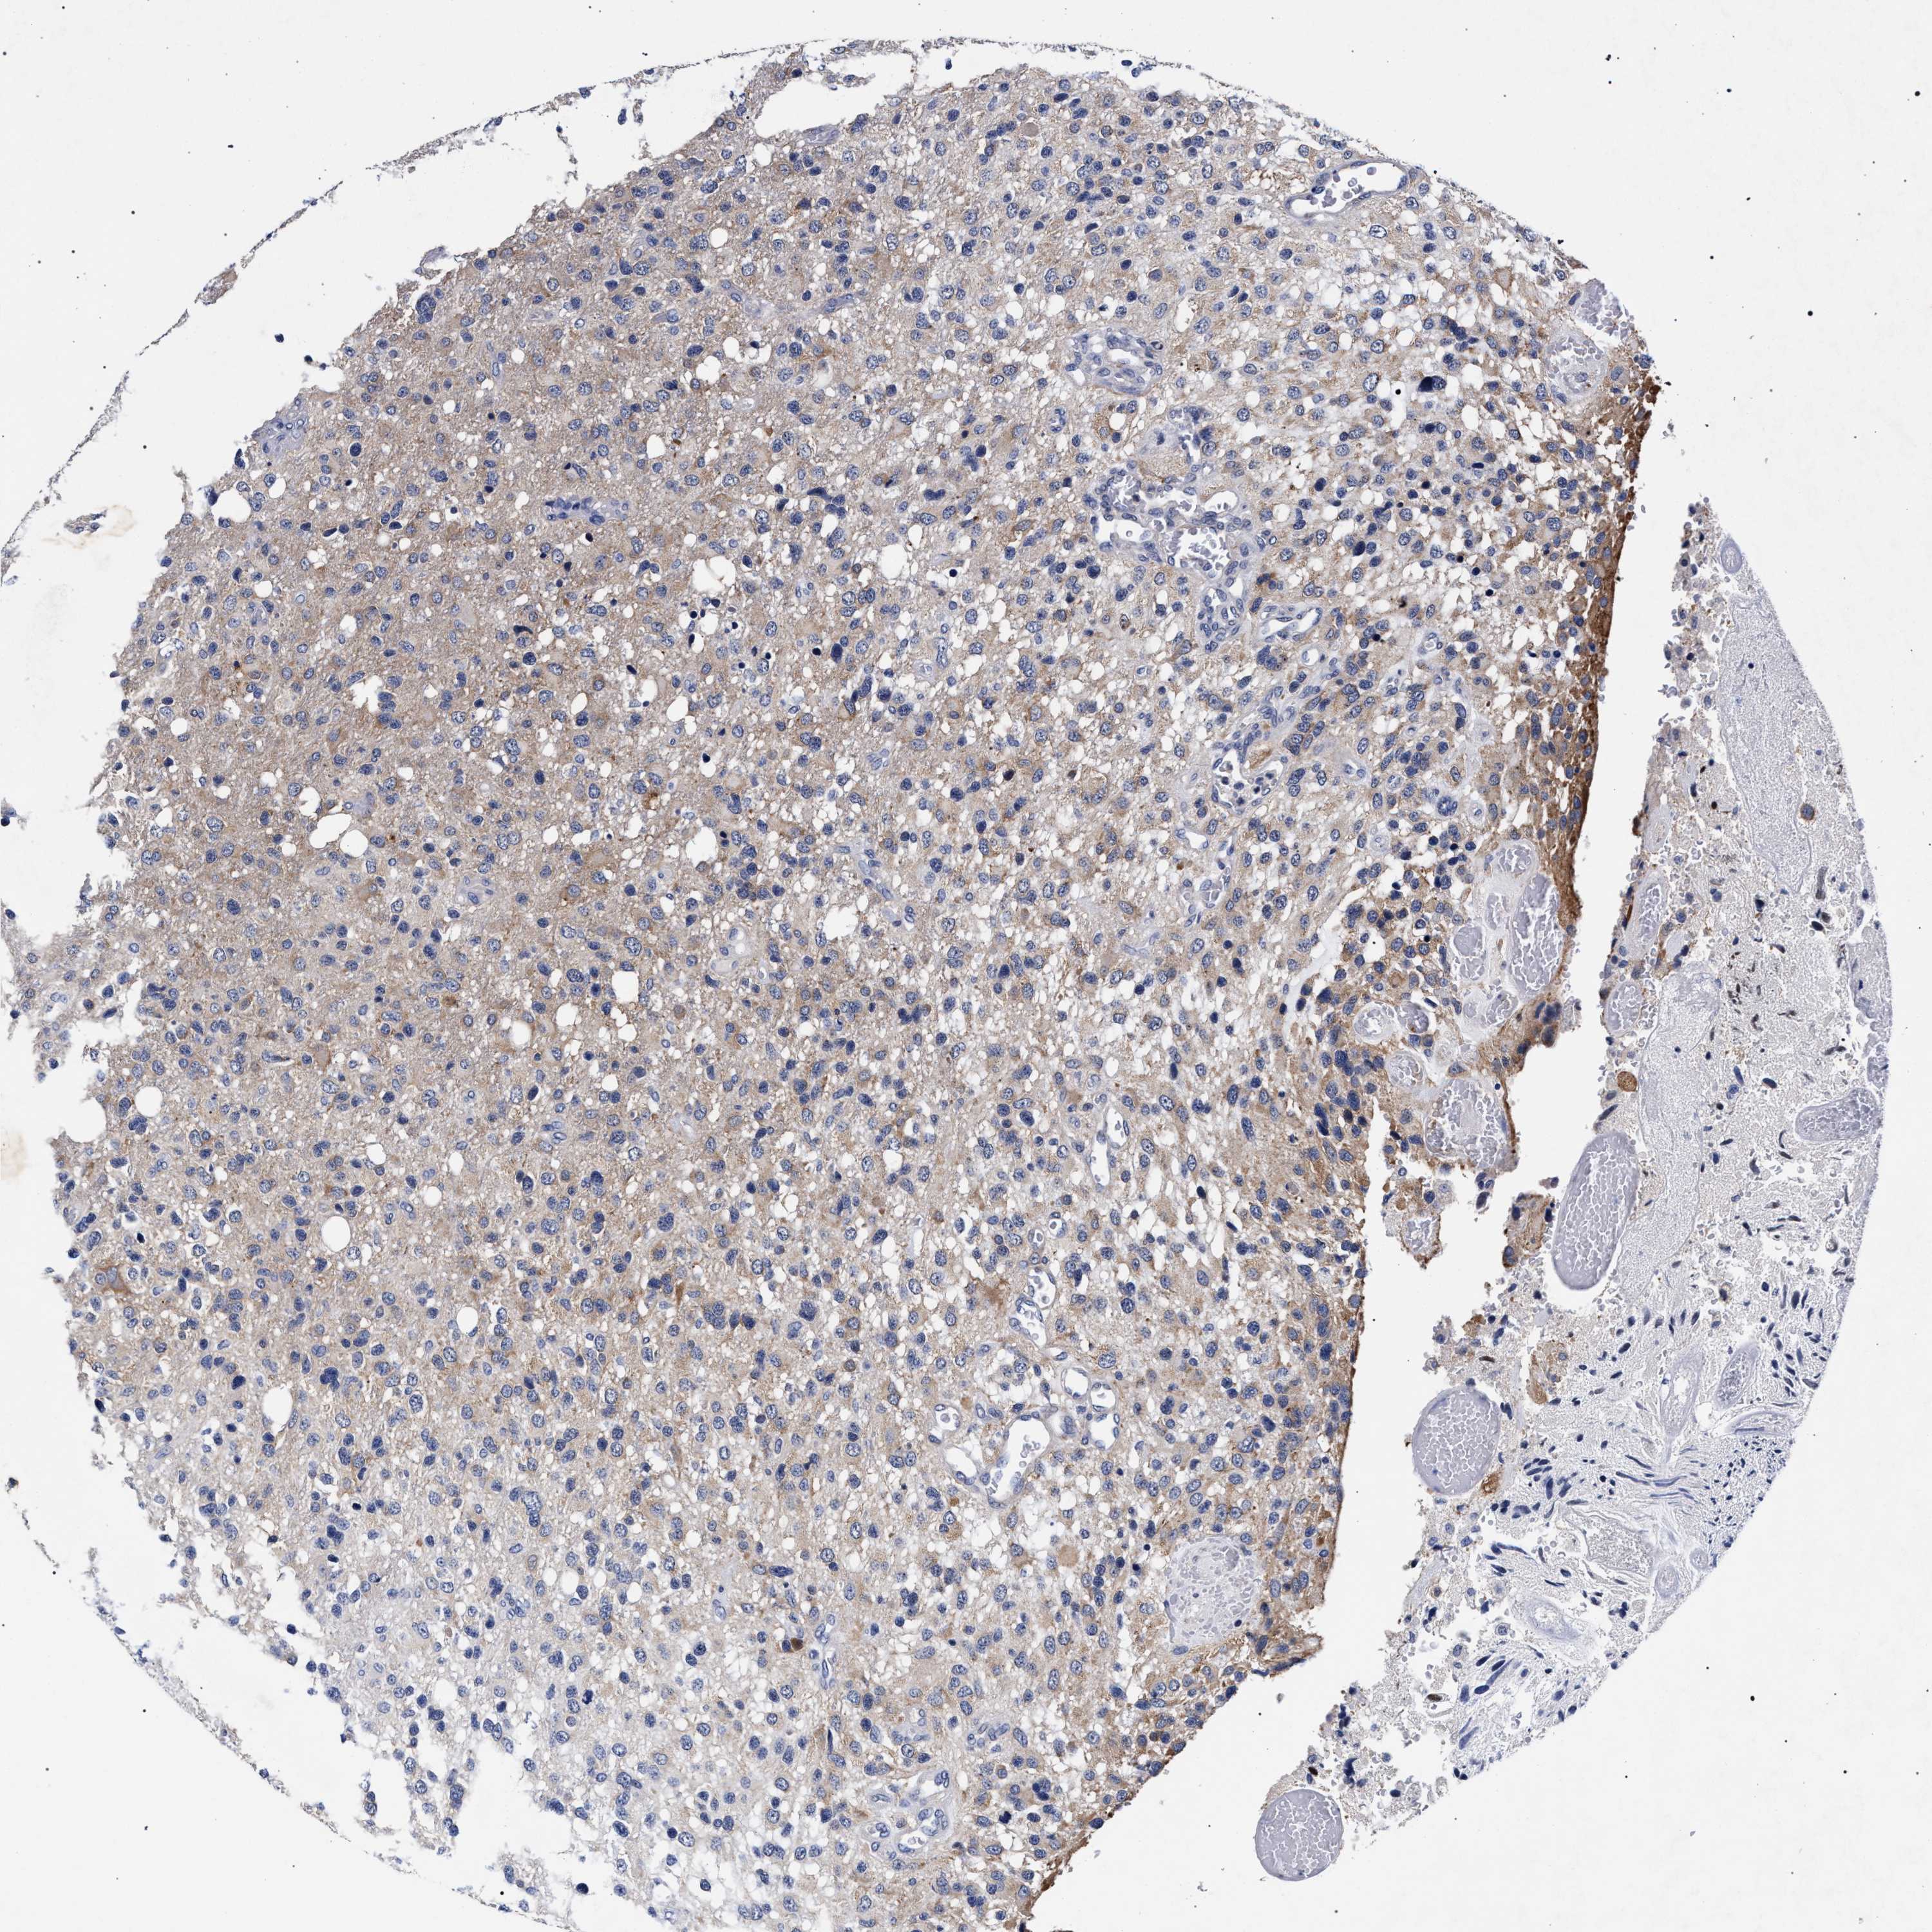

GLIOMA - Protein expressioni

A mouse-over function shows sample information and annotation data. Click on an image to view it in a full screen mode. Samples can be filtered based on level of antibody staining by selecting one or several of the following categories: high, medium, low and not detected. The assay and annotation is described here.

Note that samples used for immunohistochemistry by the Human Protein Atlas do not correspond to samples in the TCGA dataset.

Antibody stainingi

Antibody staining in the annotated cell types in the current human tissue is reported as not detected, low, medium, or high, based on conventional immunohistochemistry profiling in selected tissues. This score is based on the combination of the staining intensity and fraction of stained cells.

Each image is clickable and will lead to virtual microscopy that enables deeper exploration of all samples and also displays staining intensity scores, fraction scores and subcellular localization as well as patient and tissue information for each sample.

Antibody HPA021261

Antibody HPA021325

Staining

High

Medium

Low

Not detected

Intensity

Strong

Moderate

Weak

Negative

Quantity

>75%

75%-25%

<25%

None

Location

Nuclear

Cytoplasmic/membranous

Cytoplasmic/membranous,nuclear

Glioma, malignant, High grade

Glioma, malignant, Low grade